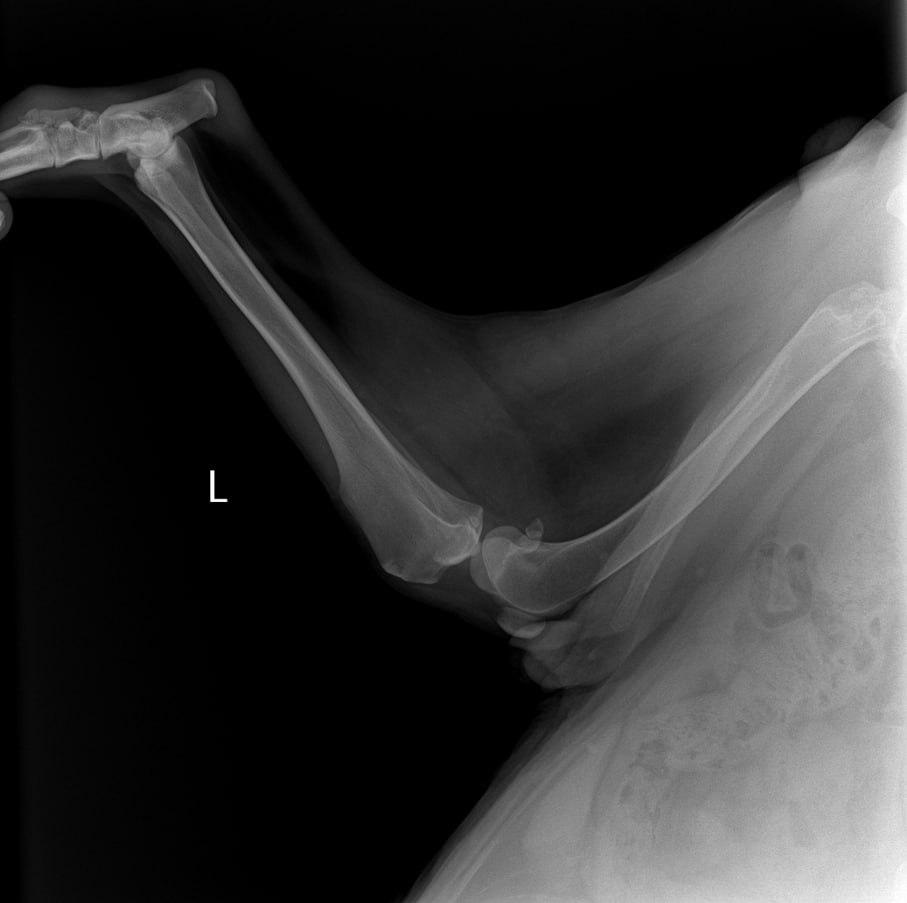

Рентген

Рентген лапы, которая болит